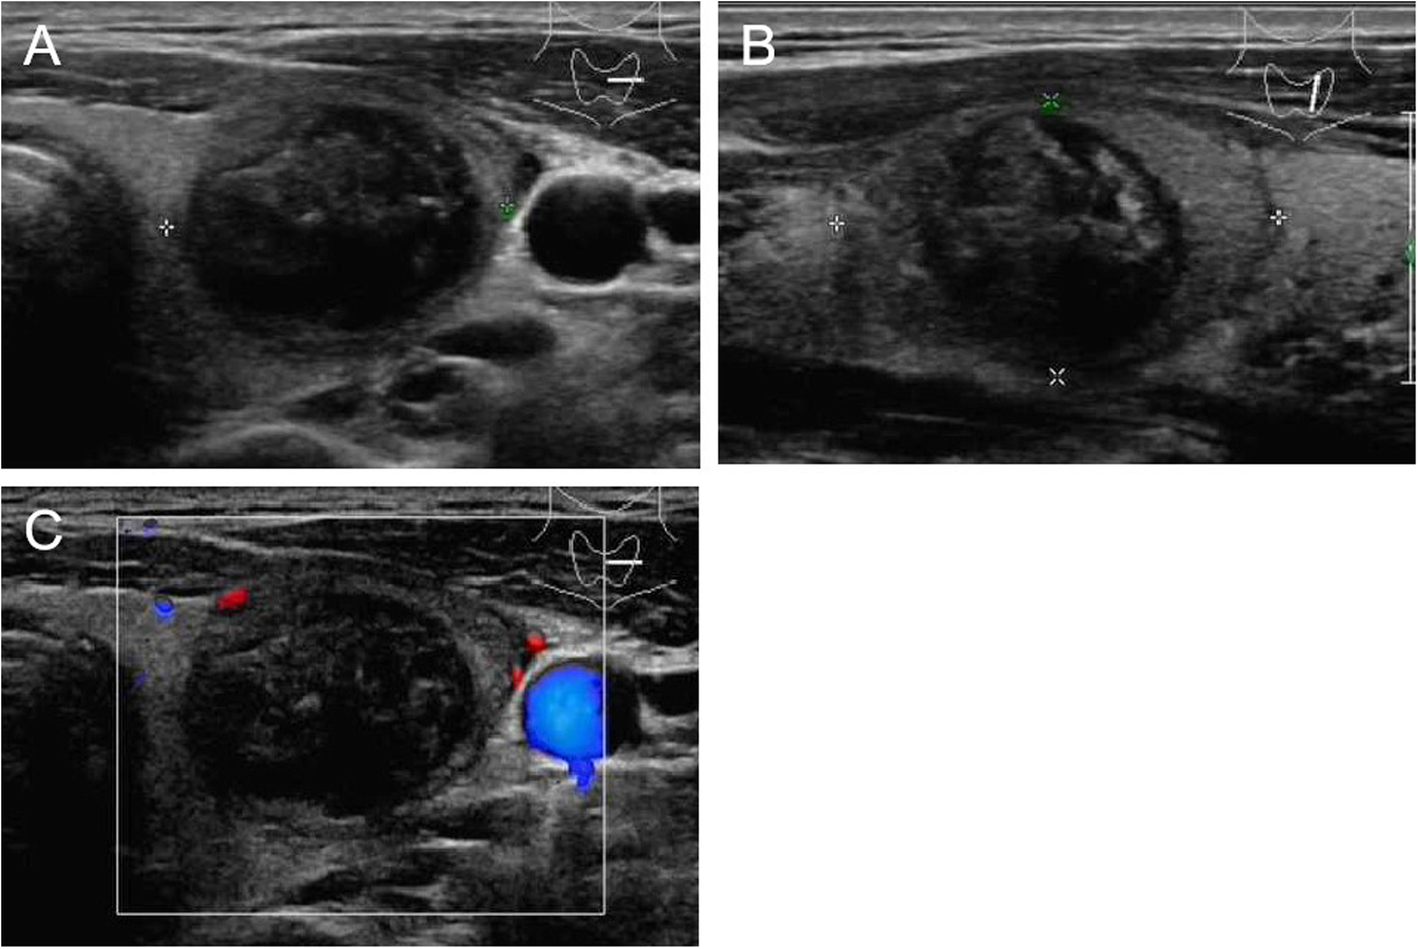

Fig. 5

From: Ultrasound features of medullary thyroid cancer as predictors of biological behavior

US images of medullary thyroid carcinoma nodules categorized by TI-RADS 3. Male patient, 40 years old, 3.06 cm × 2.36 cm × 1.85 cm. The serum calcitonin level was <2 pg/mL. a and b Lesion was solid, hypoechoic, ill-defined, ovoid to round in shape, microcalcifications. a A/T < 1. c Absent blood flow